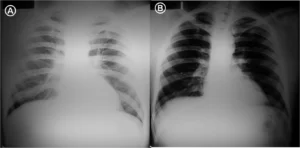

4.5 Cardiomegalia y edema pulmonar

El aumento del ICT es el dato clave. Un ICT > 0,5 en un adulto o ICT > 0,55 en un niño, indica un aumento del tamaño del corazón. En este video puedes ver una Rx de torax en un paciente con cardiomegalia. Pero siempre debes correlacionar con los datos del paciente.

Edema pulmonar: líneas B de Kerley, redistribución vascular y patrón “en alas de mariposa”. Estos signos indican grados sucesivos de aumento de la presión venosa pulmonar.